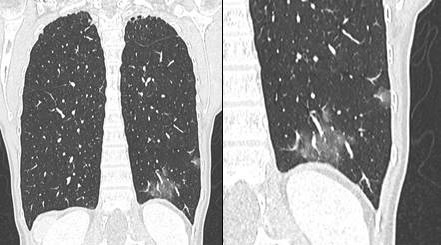

- Des opacités en « verre dépoli » bilatérales sous pleurales postérieures (Fig. 1)

Figure 1 : Aspect de verre dépoli de la base gauche. Anomalies débutantes.

Figure 2a : Aspect de « crazy paving » (mosaïque) des deux bases chez un patient de 43 ans, PCR +.

Figure 2b : aspect de condensation parenchymateuse linéaire de la base gauche, le même patient.